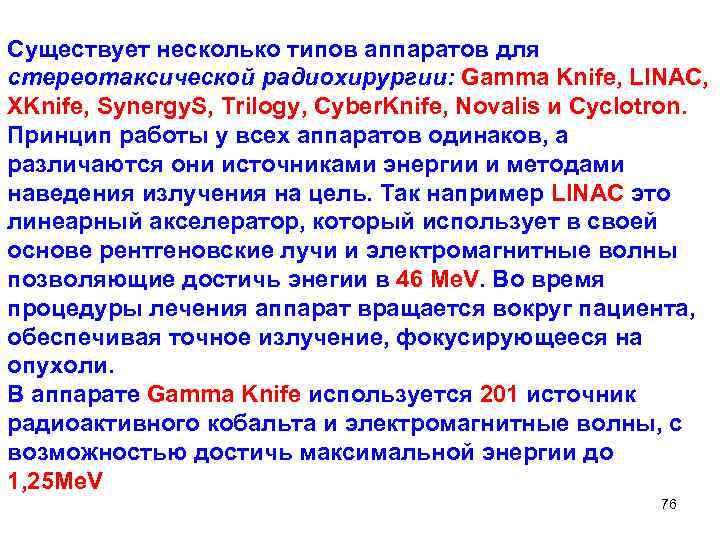

Существует несколько типов аппаратов для стереотаксической радиохирургии: Gamma Knife, LINAC, XKnife, Synergy. S, Trilogy, Cyber. Knife, Novalis и Сyclotron. Принцип работы у всех аппаратов одинаков, а различаются они источниками энергии и методами наведения излучения на цель. Так например LINAC это линеарный акселератор, который использует в своей основе рентгеновские лучи и электромагнитные волны позволяющие достичь энегии в 46 Me. V. Во время процедуры лечения аппарат вращается вокруг пациента, обеспечивая точное излучение, фокусирующееся на опухоли. В аппарате Gamma Knife используется 201 источник радиоактивного кобальта и электромагнитные волны, с возможностью достичь максимальной энергии до 1, 25 Me. V 76